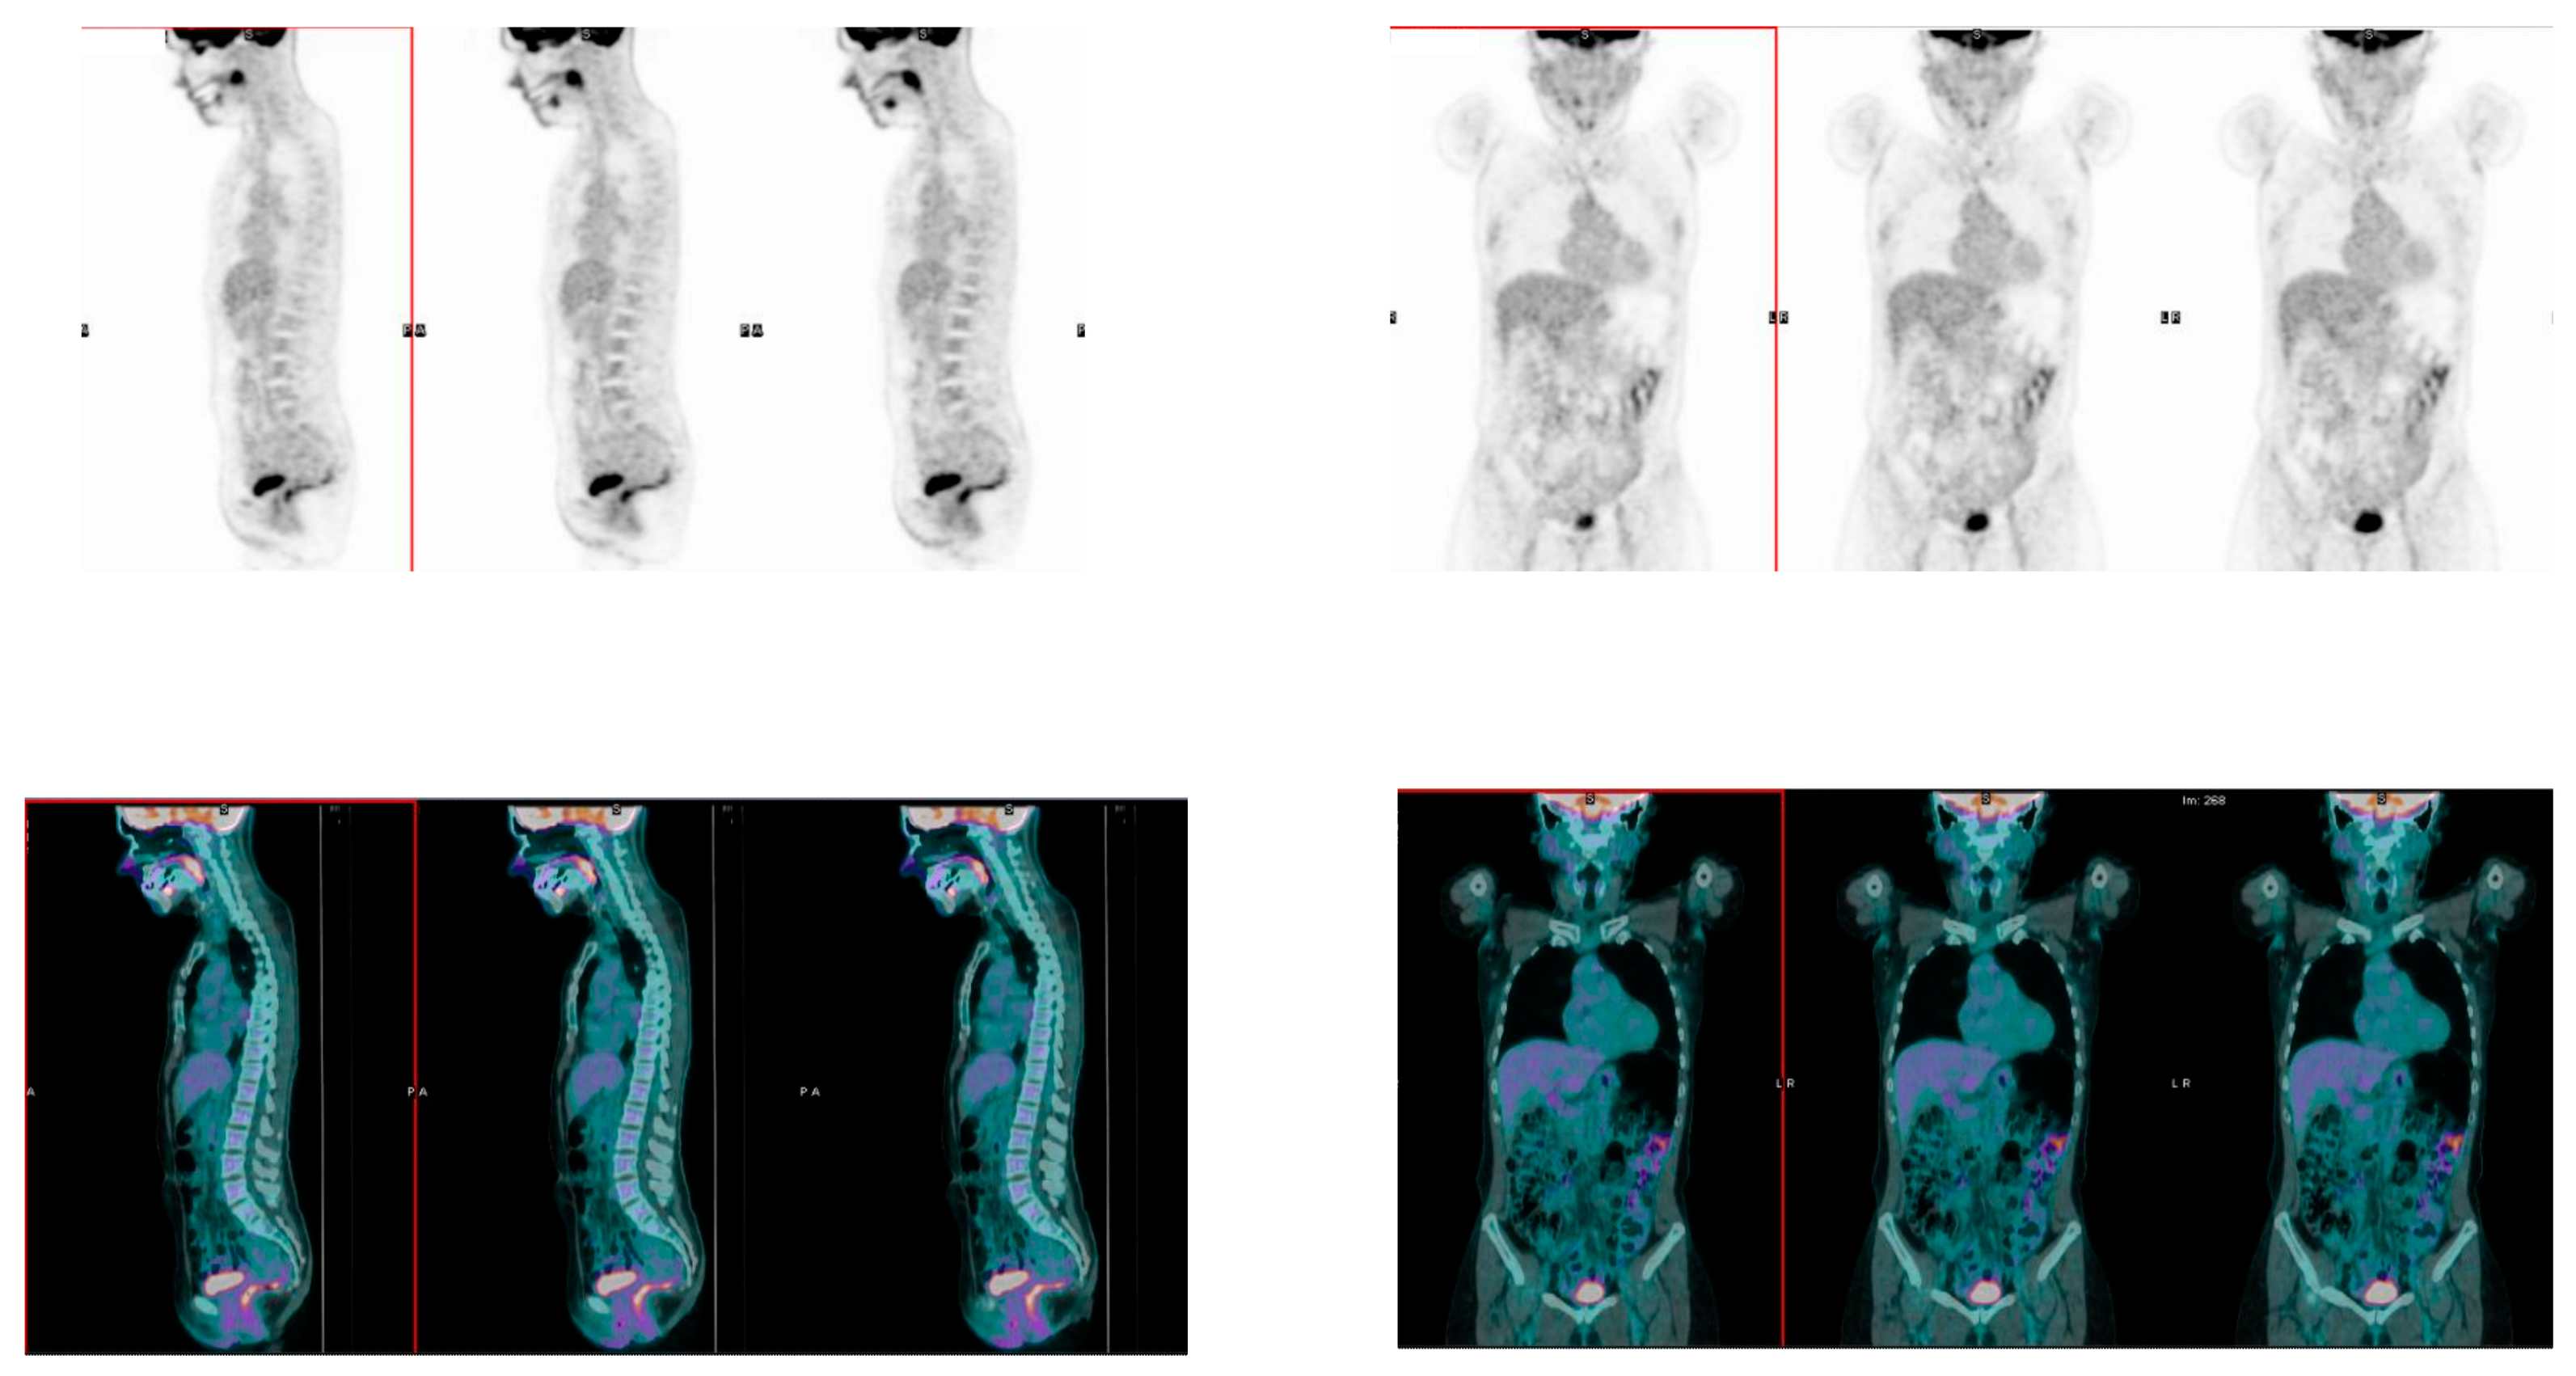

2.3. [18]F-FDG PET/CT Acquisition Protocol